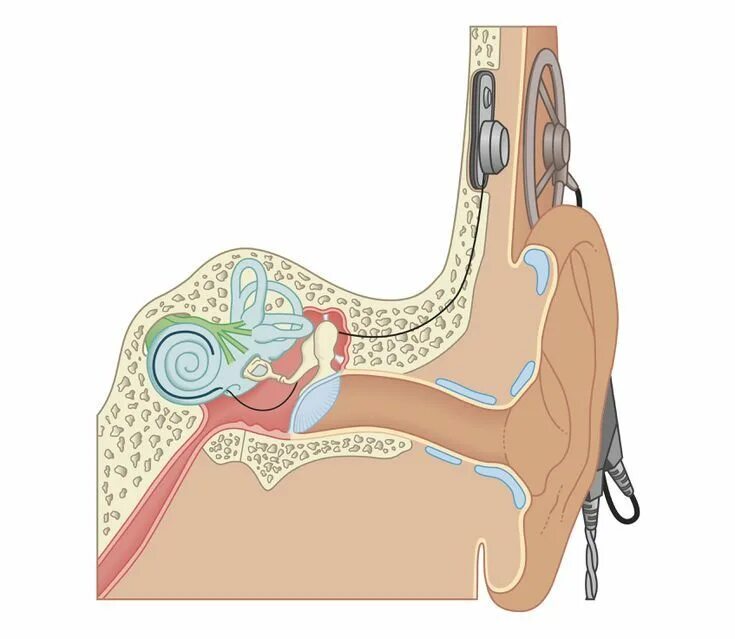

Кохлеарный отосклероз